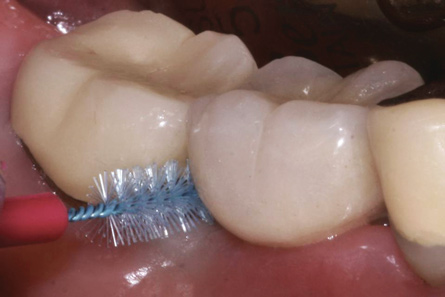

Prosthetic reconstructions should allow for proper personal cleaning, clinical diagnosis by probing, and professional plaque removal.7,35 The provision of proper oral hygiene instructions to patients reduces the risk of peri-implant disease development.35,37 Use of a manual or powered toothbrush by the patient was found to be effective in preventative plaque control.7 Interdental oral hygiene aids, such as interdental brushes and water jets (Figure 8), ranked high for reduced gingival bleeding around teeth.37 Abutment and crown design should facilitate use of these oral hygiene aids as well as professional supportive therapies. Conversely, convex emergence profiles and interdental embrasure spaces that impede accessibility for plaque removal should be avoided.

Fig 8. Adequate space has been provided to permit insertion of an interdental brush mesial and distal to implant site No. 30.

Figure 8